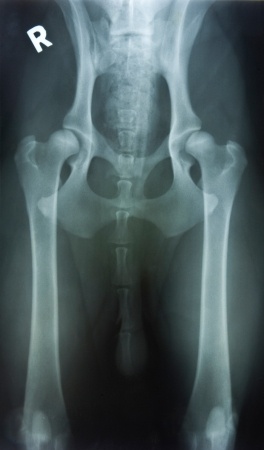

If you suspect that your dog has hip dysplasia, the first step is a visit to the veterinarian. The veterinarian will begin with a standard physical exam which might include urinalysis, a blood chemical profile, an electrolyte panel, and a blood count. He may also look over your dog’s medical records and their family history to determine if your dog is genetically prone to developing this disease.

Depending on these results, your veterinarain may suggest further diagnostic procedures such as X-rays, which would help confirm their analysis with an image of the joint in question. An abnormal contour or appearance associated with the hip joint would support the diagnosis of hip dysplasia.2